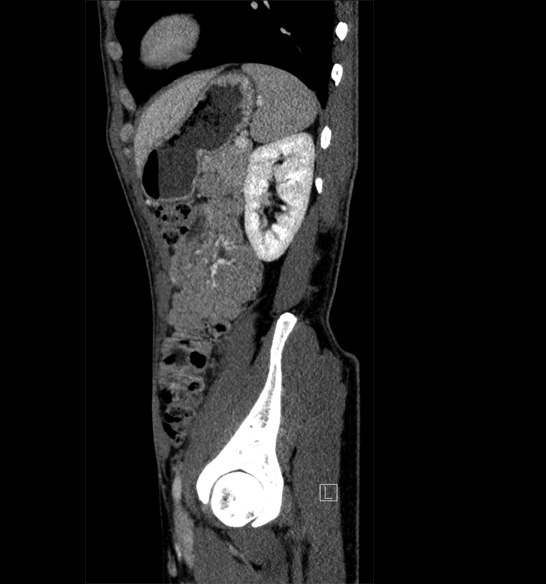

Body

Covers abdominal CT anatomy.